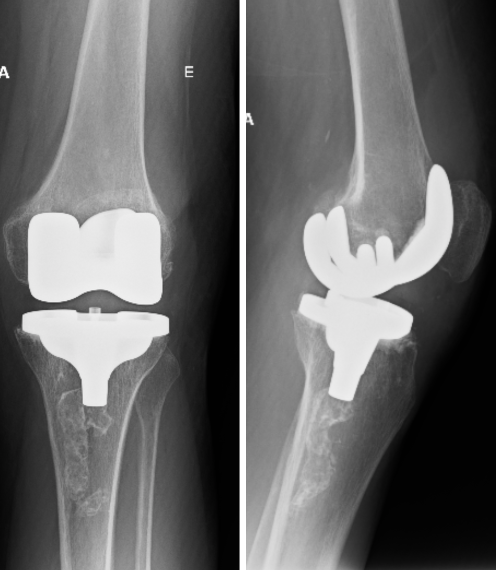

Radiografia pós-operatória de prótese total do joelho.

Figura 4 - Radiografia pós-operatória de prótese total do joelho.

Quando os tratamentos conservadores não são mais suficientes para controlar os sintomas, a cirurgia pode ser a melhor solução:

• Artroplastia (Prótese de Joelho): É a substituição da articulação danificada por um implante artificial. Pode ser parcial (quando apenas uma parte do joelho é substituída) ou total. A prótese é um dos procedimentos mais bem-sucedidos da medicina moderna, oferecendo alívio duradouro da dor e a restauração da função para pacientes com artrose avançada.